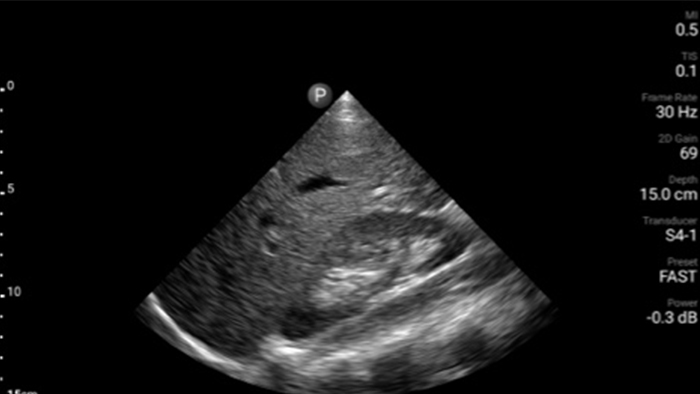

Respond fast with whole-body imagery

Lumify can help you assess patients from head to toe, whether it’s plantar fasciitis, tendonitis or bursitis in the patellar tendon, or even shoulder instability in the rotator cuff.